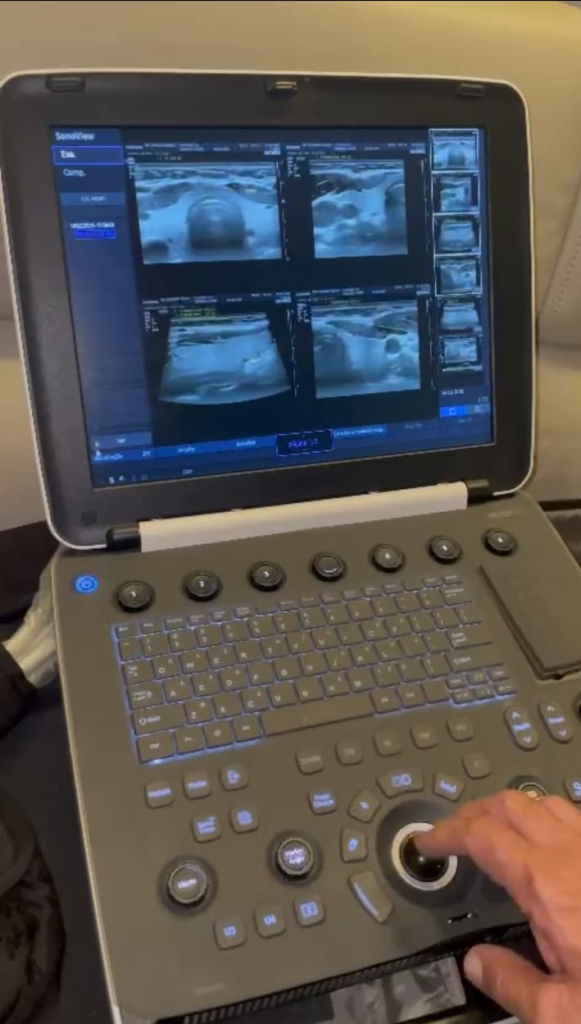

Ultrassom Samsung HM70 EVO com as 3 sondas gerais

* Máquina HM70 EVO********

03 sonda: convexo, endocavitária e linear ( LA3 - 16 AD).

03 sonda: convexo, endocavitária e linear ( LA3 - 16 AD).